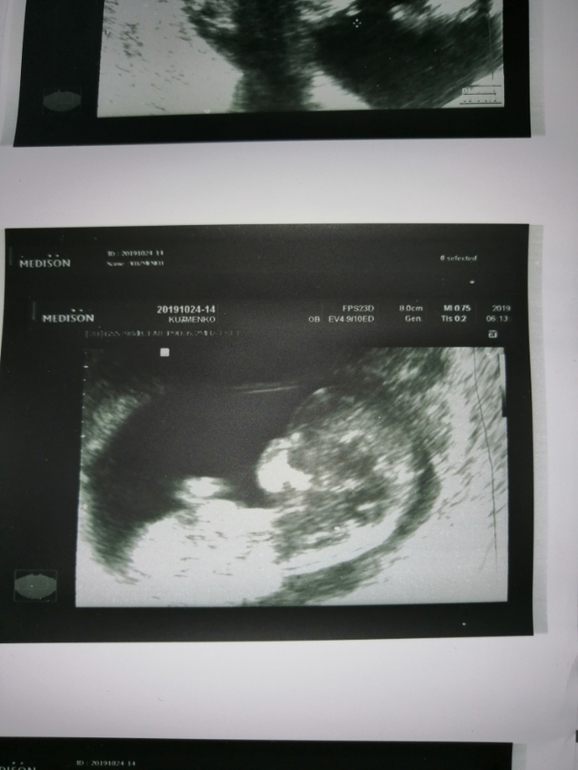

В общем про скрининг. Зашла в кабинет, лягла, смотрит вагинально, странно смотрела, потом ей что то стукнуло в голову и она начала мне этим датчиком тыкать в матку со словами "что то он сильно спокойный, не хочет шевелиться" я ее спрашиваю, вы что не можете его измерять?

Она "нет, я всё для себя увидела, я хотела вам показать"  я говорю, что мне и так всё видно, зачем так тыкать, ответ был "для фотки". Думаю ну больная на голову," изнасиловала" датчиком)) ради фотки, матка начала болеть и поясница, в итоге из всего осмотра вымеряла ктр и твп

я говорю, что мне и так всё видно, зачем так тыкать, ответ был "для фотки". Думаю ну больная на голову," изнасиловала" датчиком)) ради фотки, матка начала болеть и поясница, в итоге из всего осмотра вымеряла ктр и твп и еще нашля омниотический тяж.

Узи с жк